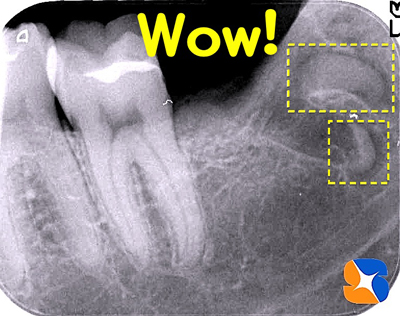

レントゲン写真の結果、親知らずの歯は、下のアゴ骨に真横に埋まっていました。更に根の先はカーブを描き、骨をホールドしています。難しい抜歯になると予測されたので、CT撮影を行いスムーズな抜歯を目指しました。

順調に抜歯を進めていたが、最終段階になって「バッキッ!」と嫌な音。直ぐにレントゲンで確認すると、2本の根の先が、両方とも折れた状態で骨の中に取り残されていました。